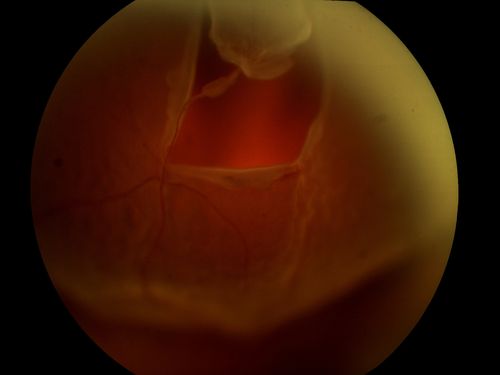

Retinal Detachment Secondary to Irregular Retinal Tear

Retinal Detachment with Irregular Retinal Tear

Retinal, Detachment, Tear, Irregular

Quad Cities Retina Consultants

Topcon TRC 50EX with OIS Winstation 5300